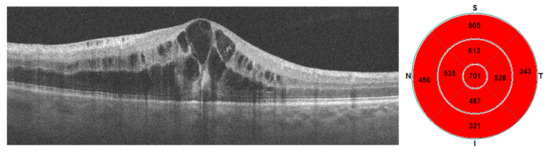

7. Examples of OCT-A Scans before and after Treatment